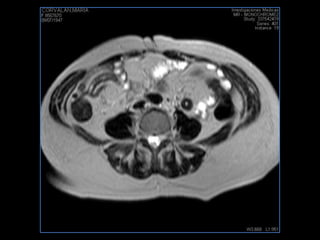

PROTOCOLO pelvis SAG T2, Y FAT SAT (FINOS) AXIAL T1  AX FAT SAT CON   GADOLINIO :  AX T1 Y COR T1 SAT: NO  FASE: RL THK: 3MM  COIL:  GAP: (FACTOR 1.4) 1MM FOV: 40 CM NEX:2 SINCRONIZACION RESPIRATORIA EN 3 O 4 CICLOS ALE

resonancia de abdomen